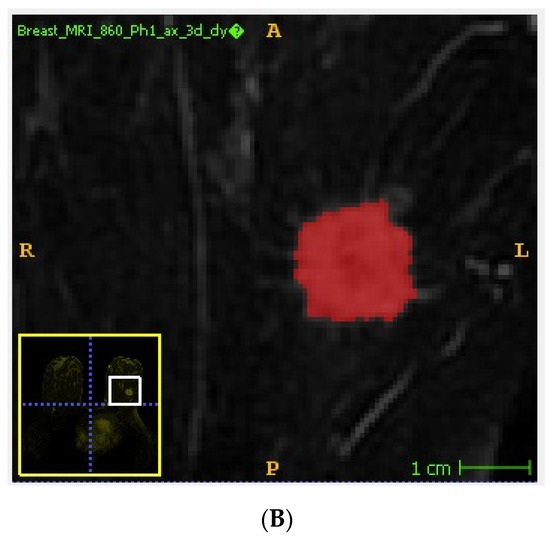

2.3. Image Analysis